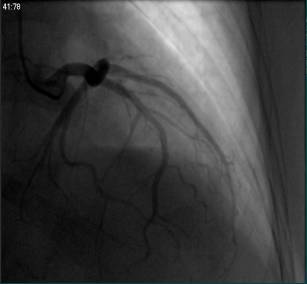

②冠脉造影:

冠脉造影未见明显异常;

⑥冠脉造影(2015.03.02)